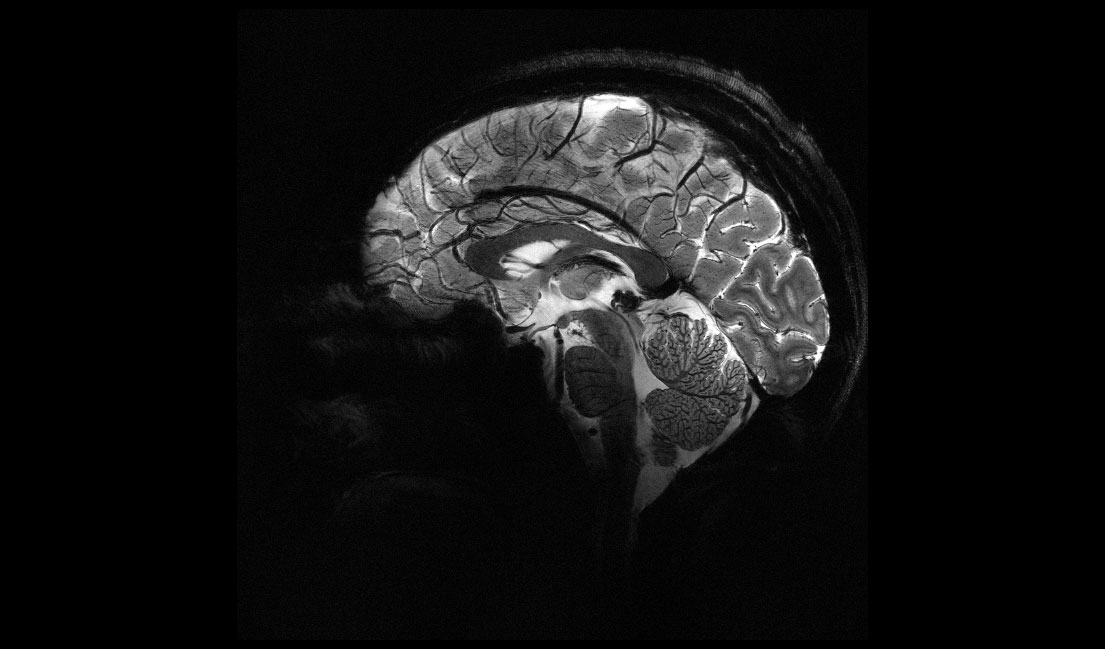

Получены самые четкие МРТ-изображения мозга за всю историю

Ученые из Французской комиссии по альтернативной энергетике и атомной энергии (CEA) представили серию изображений человеческого мозга, полученных с помощью аппарата Iseult MRI, говорится на сайте организации. Сила магнитного поля оказалась значительно больше, чем у обычных установок. Новый аппарат поможет изучить тяжелые заболевания.

Сила магнитного поля нового аппарата равняется 11,7 тесла. Мощность МРТ в обычных больницах составляет 1,5–3 тесла. Iseult MRI позволяет делать изображения в очень высоком разрешении — до 0,2 мм по горизонтали при толщине среза 1 мм. Это равняется объему, сравнимому с несколькими тысячами нейронов.